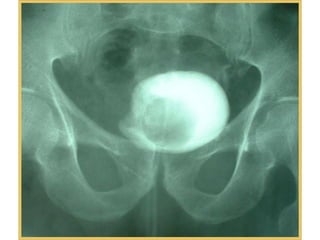

Diagnosis

• Ultrasonography: echogenic

intravesical mass

• Plain&IVU: bladder filling defect

• Pelvic and abdominal CT: confirm

and stage bladder carcinoma